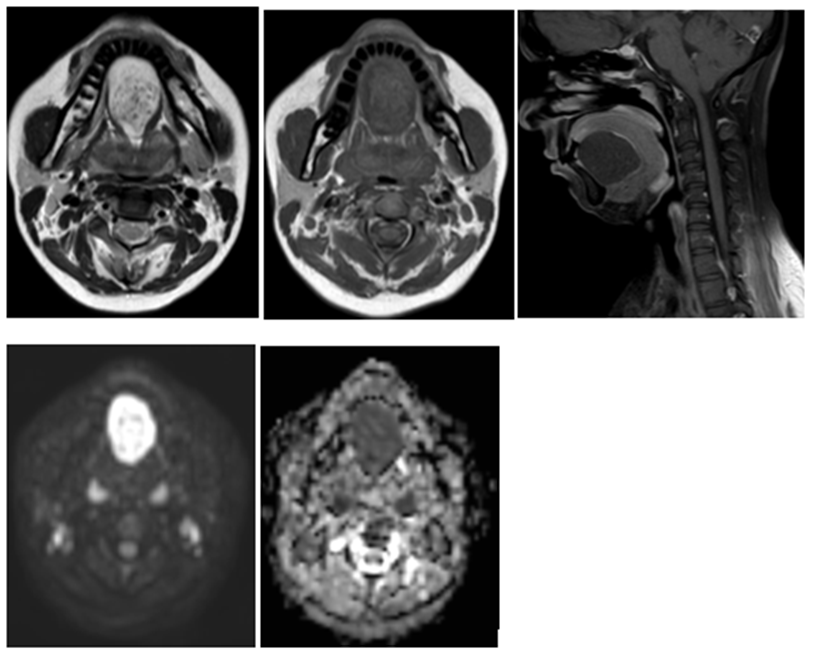

A 29-year-old woman reported a gradually increasing swelling beneath the tongue that had been present for approximately seven months. She had no pain, infection, or systemic symptoms, and the overlying mucosa appeared normal. On palpation the lesion was soft, dough like and non-tender. The mass elevated the tongue slightly, leading to mild difficulty with speech and swallowing. No abnormal lymph nodes were detected. Patient underwent magnetic resonance imaging of the neck and oral cavity which revealed a well-circumscribed cystic lesion in the sublingual region in midline above the mylohyoid muscle. The mass showed low signal on T1-weighted images, high signal on T2-weighted sequences, with minimal peripheral enhancement on post contrast images. There was significant diffusion restriction on DW/ADC images [ figure 1]. These findings were consistent with epidermoid cyst as keratin-filled cyst causes restriction of movement of water molecules. The lesion was removed surgically using an intraoral approach. Recovery was smooth, and the patient experienced no complications. Histopathologic evaluation revealed a cyst lined by keratinizing squamous epithelium with laminated keratin in the lumen, confirming the diagnosis of an epidermoid cyst.

Figure 1: A midline swelling is seen in the floor of the mouth (A – E): A. Cyst appearing hyperintense on T2W images B. Hypointense on T1W images C. displays minimal peripheral enhancement on post contrast images and D& E. restricted diffusion on DW and ADC images confirming the diagnosis of epidermoid cyst.